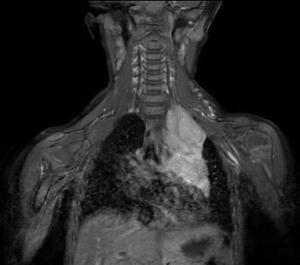

Differential diagnoses that could be considered for congenital iris heterochromia include Waardenburg syndrome and Sturge-Weber syndrome. These were excluded due to the lack of hearing loss, pigmentation abnormalities, and facial port-wine stains. Given the pupil asymmetry, iris heterochromia, and suspicion of Horner syndrome, the patient was referred to pediatric ophthalmology for further evaluation including magnetic resonance imaging. At the follow-up 3 days later with the ophthalmologist, the patient’s right pupil was measured to be 5 mm in dim lighting and 3.5 mm in bright lighting, whereas the left pupil was measured to be 3.5 mm in dim lighting and 2.5 mm in bright lighting. It was also noted that the upper lid crease of the left eye appeared fuller than that of the right eye. Magnetic resonance imaging of the head, neck, and upper thorax was recommended, which led to the discovery of a mediastinal ganglioneuroblastoma (Figure 2), resulting in a second-order Horner syndrome.